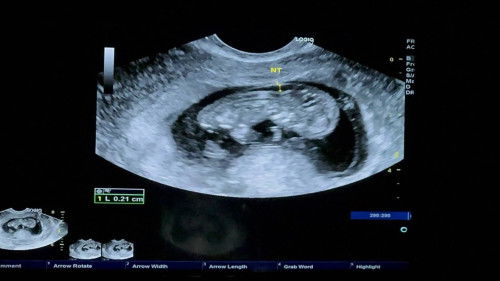

ท้องนี้ได้มาเพราะicsi ค่ะ ตรวจโครโมโซมตัวอ่อนแล้วผลออกมาปกติ ตอนนี้ตั้งครรภ์ได้10+3 ค่ะ เมื่อวานไปอัลตร้าซาวน์ หมอแจ้งว่าถุงน้ำหลังต้นคอของน้องค่อนข้างหนา แต่น้องดิ้นปกติ หัวใจเต้นปกติ โตปกติ แต่อาจมีความเสี่ยงมีความผิดปกติของโครโมโซมถึงแม้ตรวจแล้วก็ตามค่ะ หรือบางทีอาจจะเป็นถุงรกอีกชั้นนึงของน้อง เลยเป็นกังวลอย่างมาก จึงอยากขอประสบการจากทุกท่านที่มีความรู้หรือเคสประมาณนี้ ว่าความผิดพลาดเกิดขึ้นได้มากน้อยแค่ไหน หรือทารกในครรภ์จะปกติไหมคะ#ขอบคุณล่วงหน้าสำหรับความคิดเห็นค่ะ